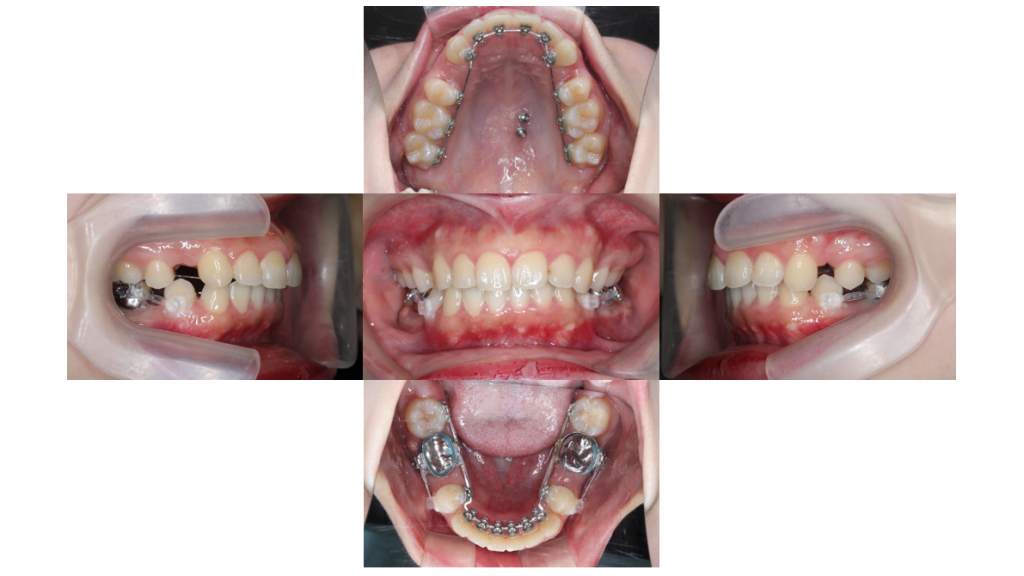

上下装置装着

上顎前突・裏側矯正の症例上下装置装着後の口腔内です